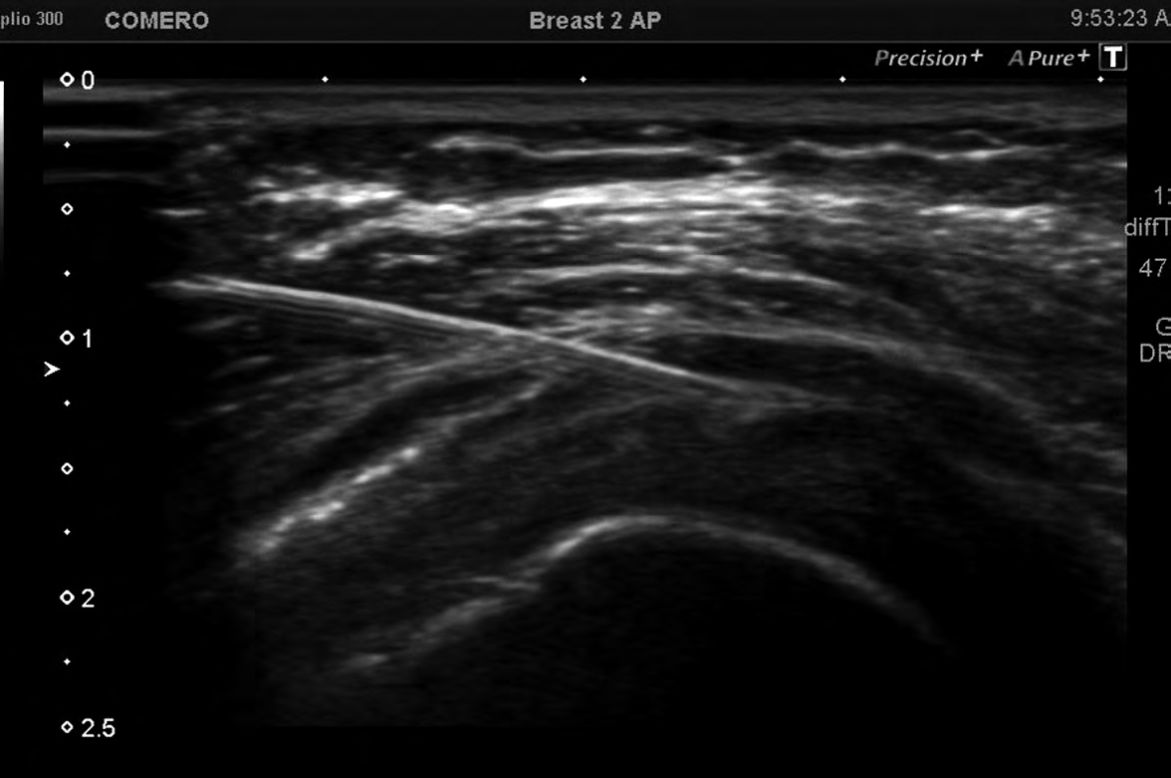

Foto 3

Punta de la aguja dentro de la articulación. Se eligió el abordaje en forma transversa. Como se ve, es una articulación pequeña, por lo que se debe administrar escasa cantidad de fármacos. Luego del procedimiento se indicó a todos los pacientes reposo funcional de la articulación por 48 horas.

Finalmente, para la articulación ACC, también en decúbito supino, se ubicó el transductor transversal o paralelo a la articulación, de manera para poder observar el extremo de la aguja al penetrar en la cápsula articular. (5-11)